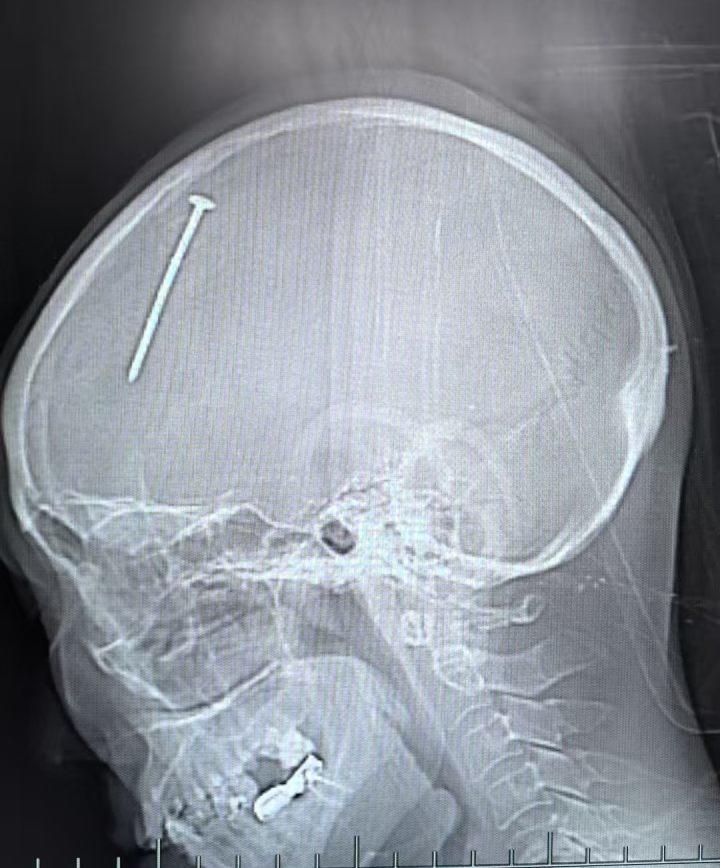

这一幕惊呆了周围的工友们,连忙叫来了120。很快,付阿姨被送到了富阳当地医院急诊。了解情况后,医生立刻为她安排了头颅 CT 检查,CT片上可以清晰地看到,一枚钢钉斜插入她的右额部,深入颅内,还伴有少量蛛网膜下腔出血。

情况十分危急,当地医院立刻将付阿姨紧急转运到杭州市第一人民医院。接到电话的急诊科陈邦医师一边接诊,一边立刻联系神经外科会诊。正在值班的神经外科副主任医师胡强立刻赶到急诊科,令他意外的是,尽管伤势严重,但付阿姨始终意识清醒,没有出现颅脑损伤常见的昏迷、呕吐等症状。但当胡强看到CT影像中那根刺眼的钢钉后,眉头拧成了 “川” 字,这手术难度极大,稍有不慎,很可能会造成二次伤害,甚至危及患者生命。

复查CT后确认,一枚钢钉从右颞部斜向插入颅内,深度达6厘米。令人惊叹的是,这枚钢钉竟精准避开了脑干、大血管、语言中枢等所有致命区域。